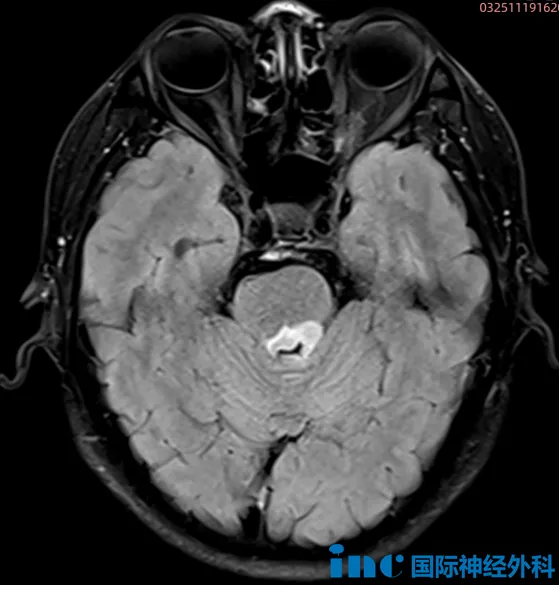

10月中旬的头颅检查结果显示:脑桥后方存在约1.8cm×1.0cm的异常信号,初步判断为脑实质肿瘤,疑似胶质瘤。周先生曾赴北京、上海多家医院就诊,均得到相似结论:"病变位置深在,手术风险极高,建议定期随访观察。"

"首先,这明确是肿瘤病变。即使是低级别肿瘤,也存在恶变可能,这是反对观望策略的有力依据。等待只会促进肿瘤生长,对患者不利。

其次,目前肿瘤在脑干内的浸润程度较浅。影像显示病变位于第四脑室表面,未深入脑干实质。若继续等待,肿瘤可能向深部进展,显著增加手术难度。

当前无症状是积极信号,说明肿瘤尚未造成永久性神经损伤。但若病情进展,神经功能可能受损,将使手术更加复杂。